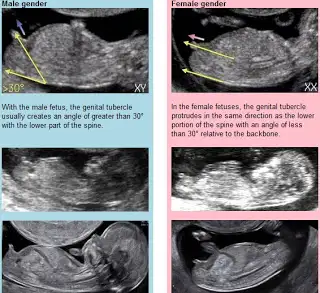

Aynen cizdigi yerden dolayi kiz dedim bak resime bende ekliyorum simdi kizlarda düz asagi yada hafif yukari gidiyo erkeklerde yukari dikine gidiyorÇizen bile oldu

Bak burds sizin resimle sag alttaki resim ayni gibiTamam teşekkürler peki o çizilen kordon olabilir mi

30 derecelik aci yok sizde yine tabi allah bilir bu teori dogrimu degilmi bilmiOrumTamam teşekkürler